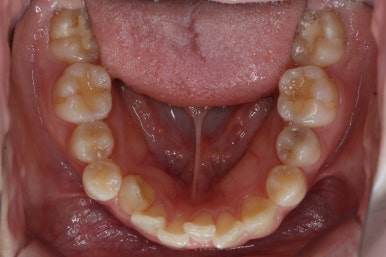

위 사진은 연산동교정치과 처음 내원하셨을 때의 입안 모습입니다. 몇 가지 모습이 관찰됩니다.

치아가 삐뚤삐뚤합니다.

위~아래 앞니가 많이 겹쳐서 아랫니가 많이 모이지 않는 "과개교합" 입니다.

앞니가 앞으로 뻐뜨러져 있습니다.